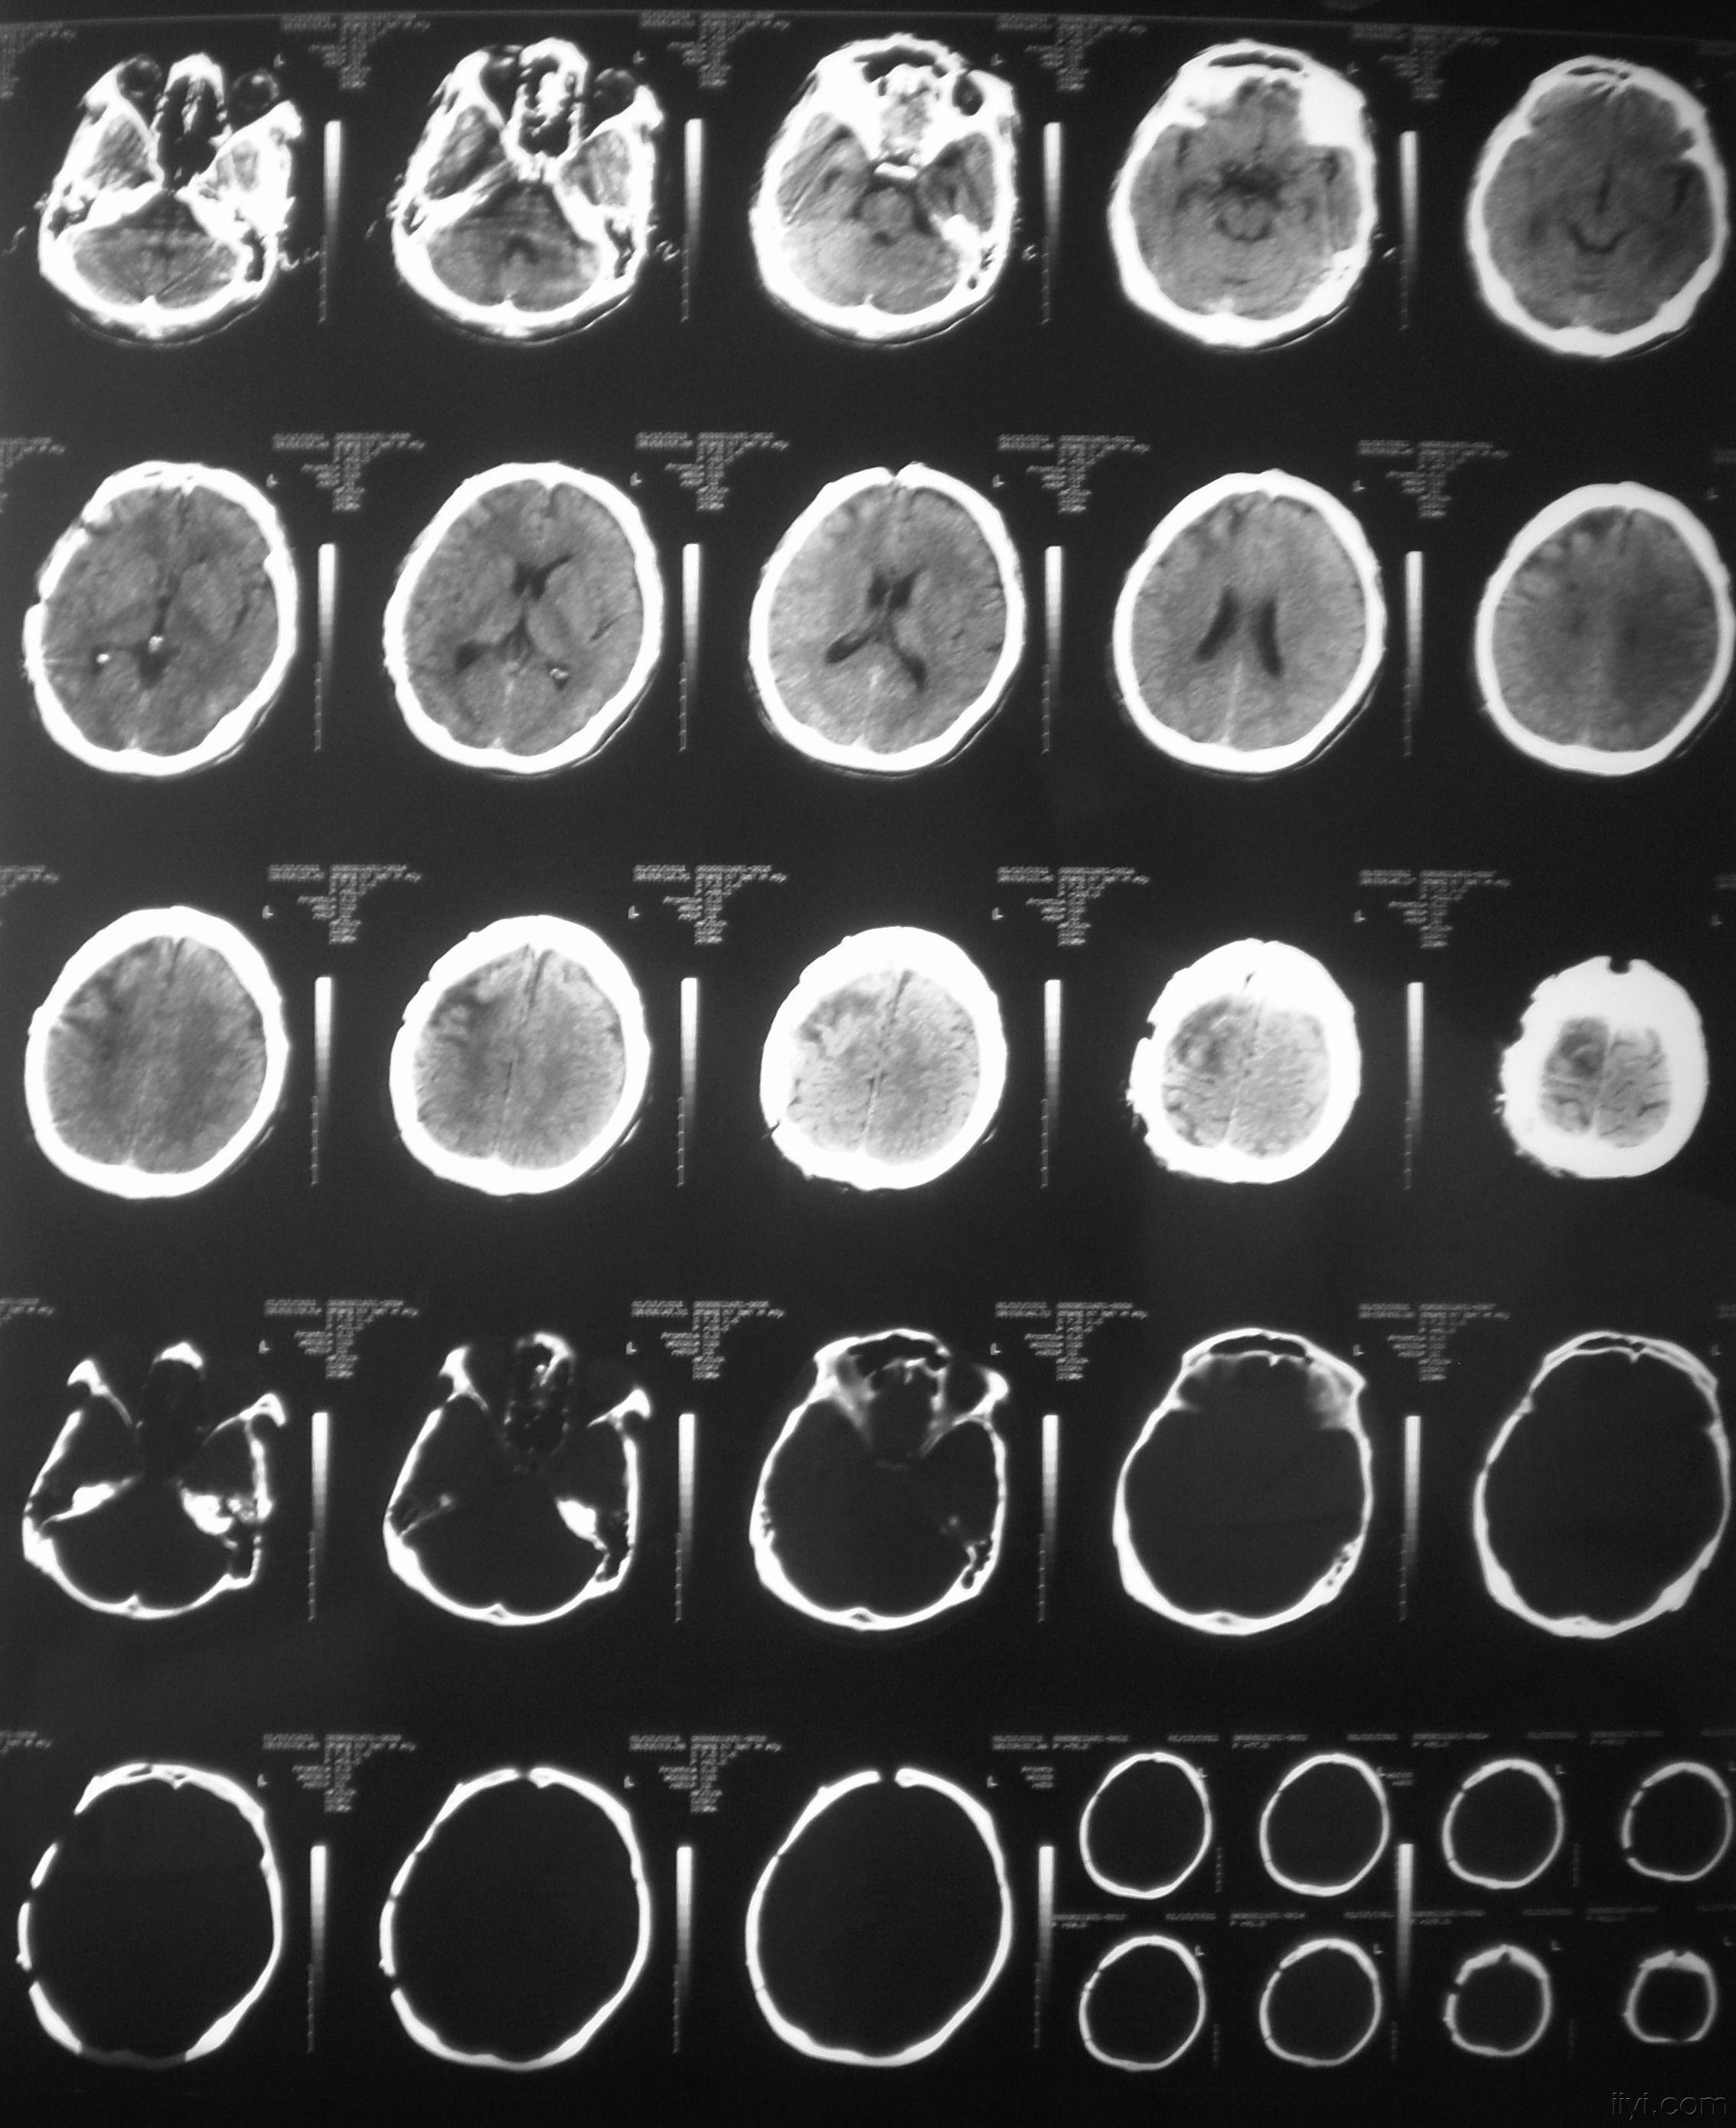

分享重型颅脑损伤双侧去骨瓣病例1则

重型颅脑损伤一例分享.

刘主任组21床重型颅脑损伤术后汇报

分享一例重型开放性颅脑损伤病例原创

一例重度颅脑损伤患者的坎坷救治历程,欢迎大家来找茬!

一例重度颅脑损伤患者的坎坷救治历程欢迎大家来找茬病情已更新请关注